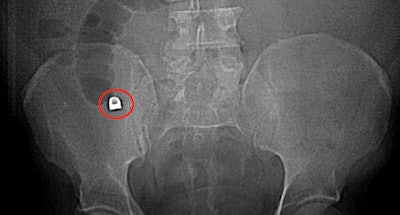

Imaging revealed a 1 x 0.9 cm metallic density in the man's appendix, as well as inflammatory findings consistent with acute appendicitis. Imaging also showed a lack of normal muscle contractions in the intestines in the man's regional right lower quadrant, the authors wrote.

An abdominal x-ray revealed a 1 x 0.9 cm metallic density, which ended up being a dental crown, in the appendix near its origin in the cecum. Images courtesy of Brennan et al. Licensed by CC BY 4.0.